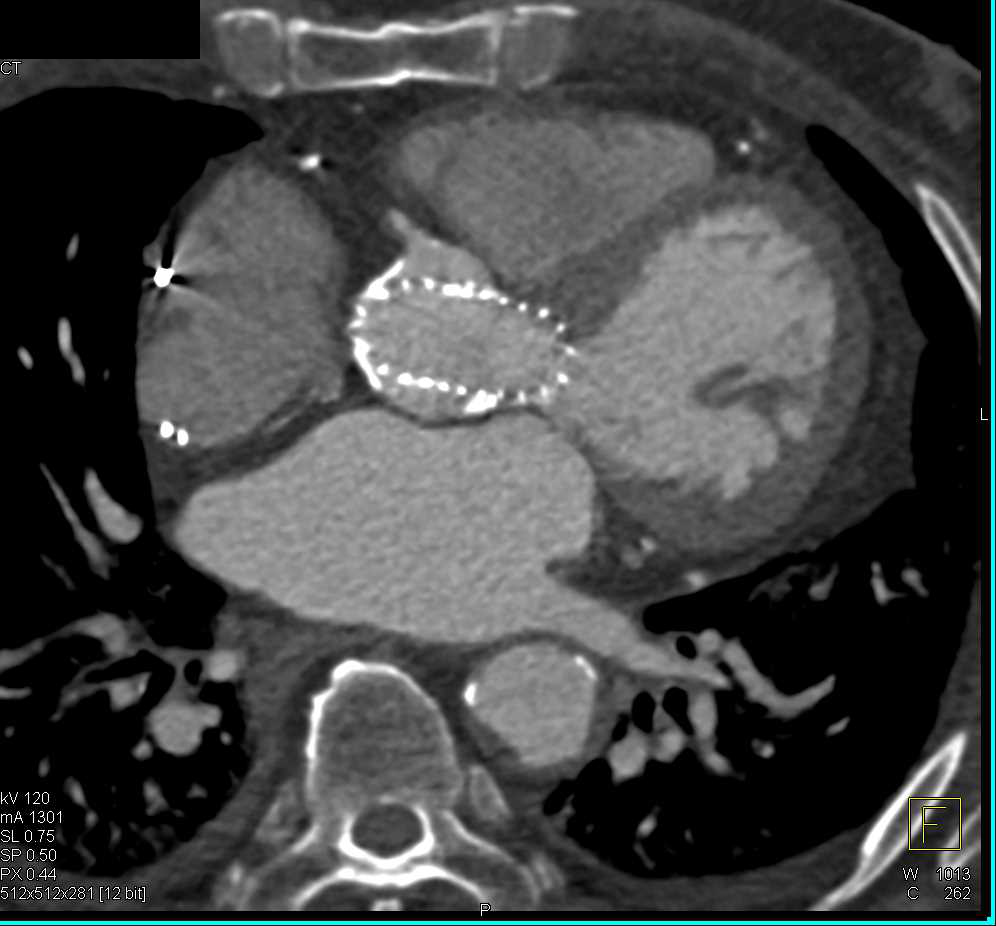

CTA with 3D of Aortic Valve Replacement (AVR)